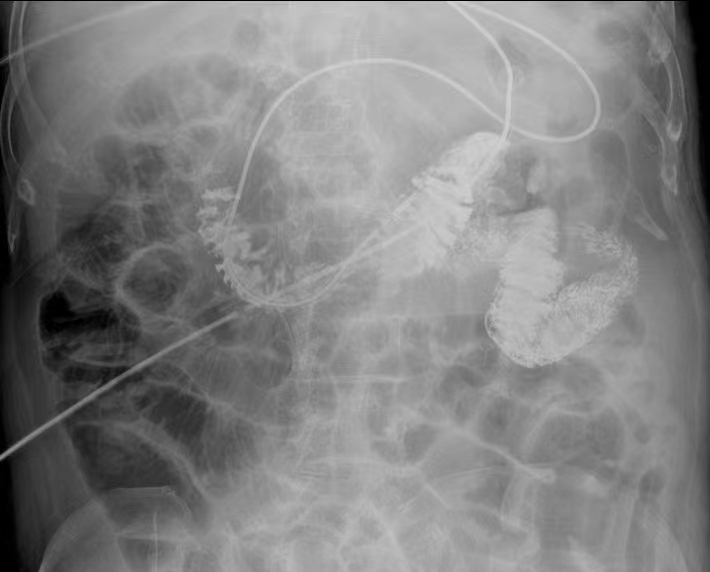

近日,常熟市第二人民医院重症医学科冯玉峰主任团队联合消化内科成翠娥主任团队成功开展首例床旁经皮内镜下胃空肠造瘘术(PEG-J)。

PEG-J可以很好的解决一周内无法肠内营养的问题。在完成胃造瘘后,在胃镜辅助下,于体外将小肠管经PEG管置入,利用胃镜将小肠管置入患者十二指肠远端(距离幽门约60cm),固定在患者腹壁,确认小肠管位置,术闭即可开始肠内营养。